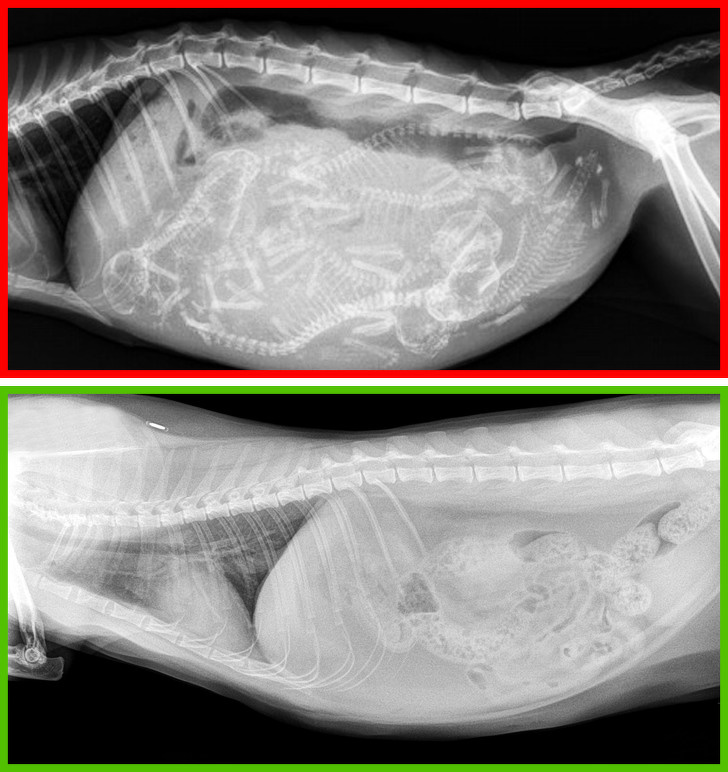

Kısırlaştırmayı reddetmek . çoğu durumda, bu prosedürlerin bir kedinin sağlığı üzerinde olumlu bir etkisi vardır. dişi kedilerde meme tümörleri ve erkek kedilerde testis tümörleri riskini azaltır. dahası, kısırlaştırılmış kediler saldırganlığa eğilimli değildir veya evden kaçmazlar.